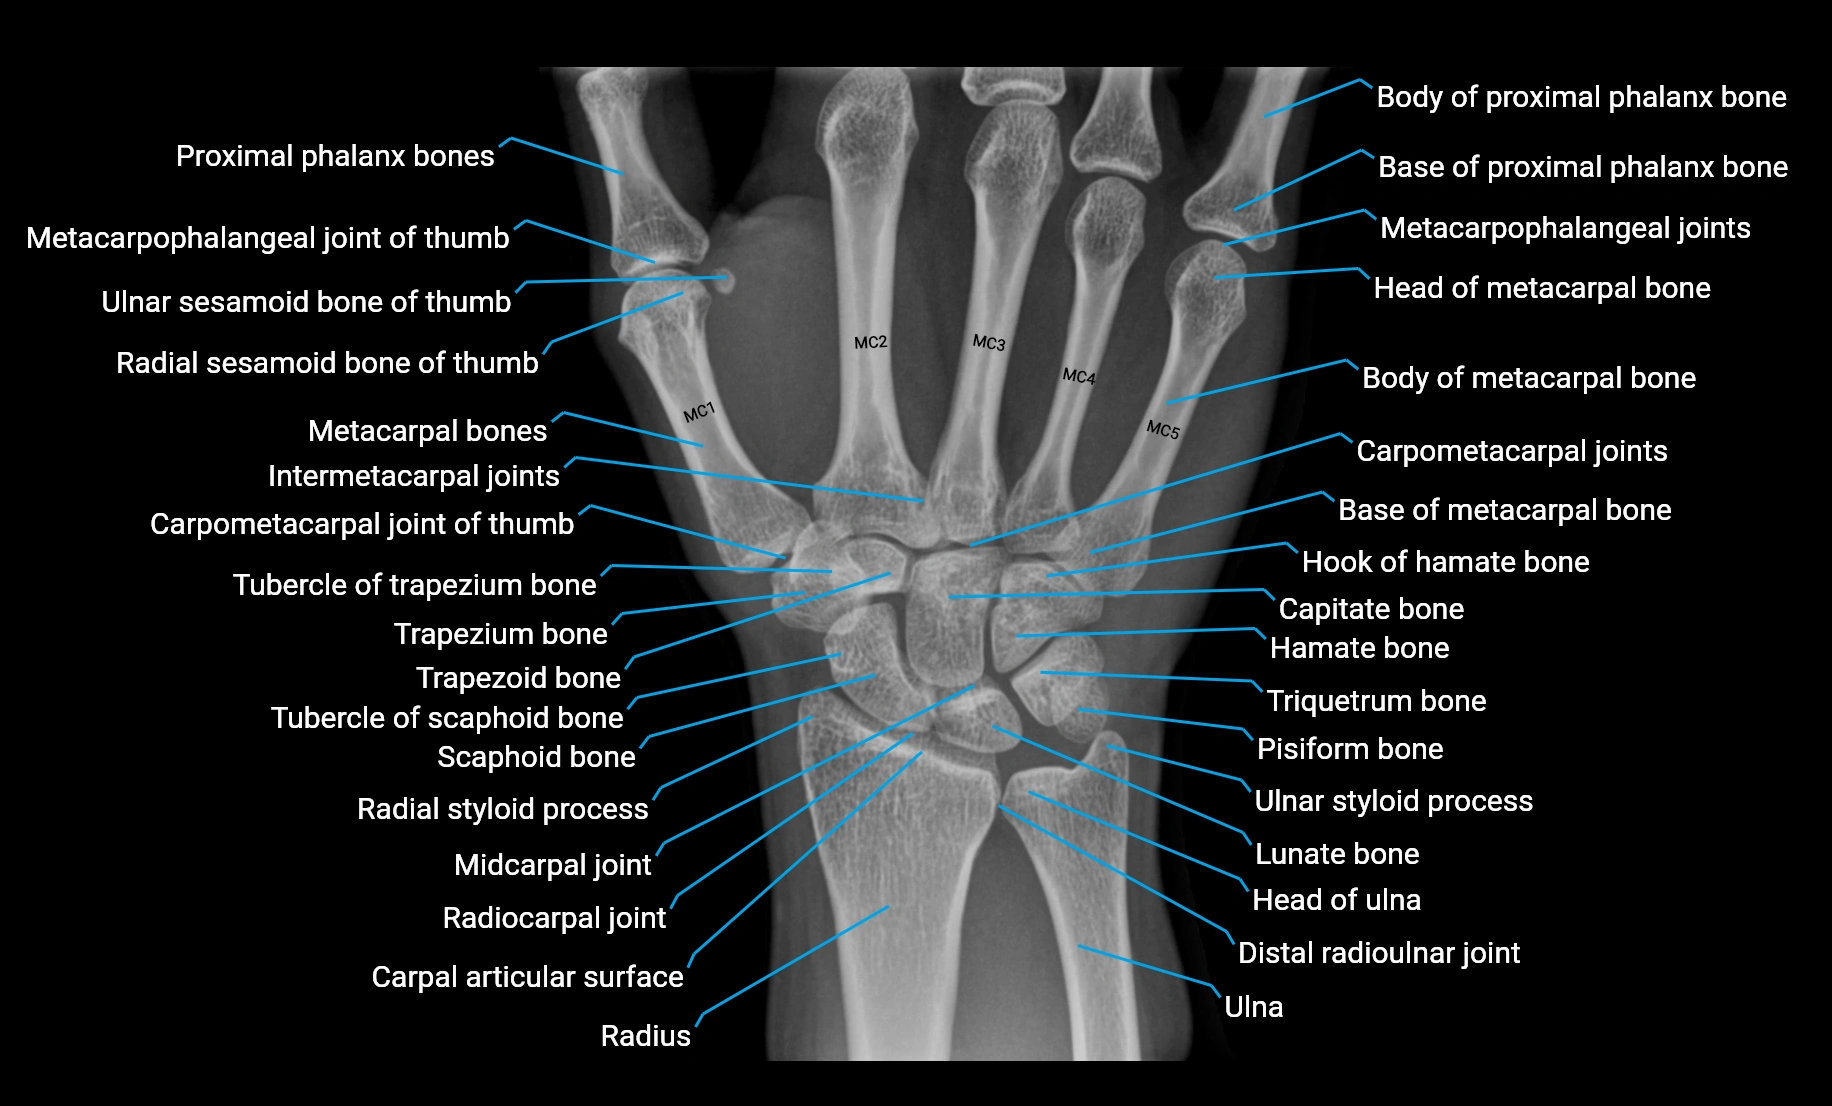

Origin: From the pisiform bone, the pisohamate ligament, and the tendon of the flexor carpi ulnaris.

Course: Muscle fibers run distally along the ulnar side of the hand, forming a flat tendon near the base of the little finger.

Insertion: Ulnar side of the base of the proximal phalanx of the fifth digit and the extensor expansion of the same finger.

• The tendon passes along the medial side of the fifth metacarpal and inserts into both the base of the proximal phalanx and dorsal digital expansion.